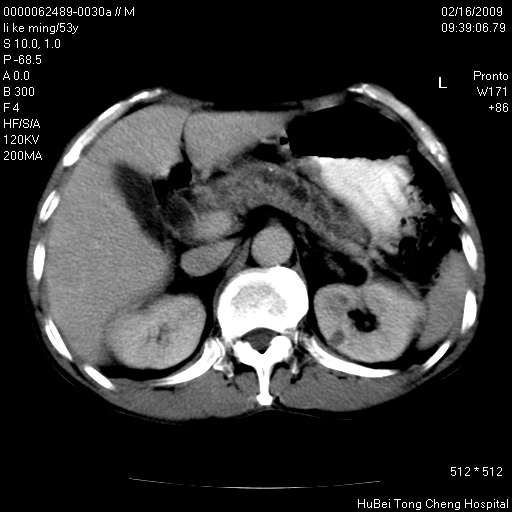

以下是引用dyqct在2009-2-16 16:58:00的发言:[br]胰头内斑点状及结节状高密度影是钙化灶还是其它?以往做过什么治疗?

以下是引用zsl6918在2009-2-17 8:48:00的发言:[br]符合胰头癌侵犯十二指肠。